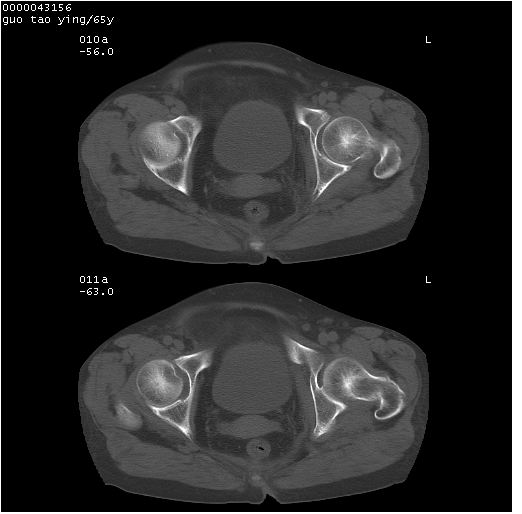

以下是引用黑白光影在2008-1-30 13:22:00的发言:[br]支持左耻骨骨折。[br]未见骶骨骨质明确破坏改变。[br]经楼主提示(勿局限于外伤)。考虑为右侧腹股沟直疝。[br][br][br][br]